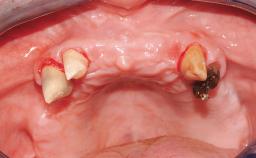

A 35-year-old Caucasian female presenting with advanced periodontal disease involving both the maxillary and the mandibular dentition was referred for evaluation. The patient, a non-smoker in good general health, requested treatment for recurrent periodontal abscesses, tooth mobility, and discomfort during chewing, as well as restoration of her missing teeth with a fixed prosthesis to improve mastication and esthetics. All residual maxillary teeth exhibited plaque deposits, deep pockets, bleeding on probing, and class III mobility and were evaluated as hopeless. All residual mandibular teeth except tooth 37 could be maintained after periodontal therapy.

| Bone Augmentation | Horizontal|Staged|Vertical |

| Augmentation Materials | Autogenous block(s) |